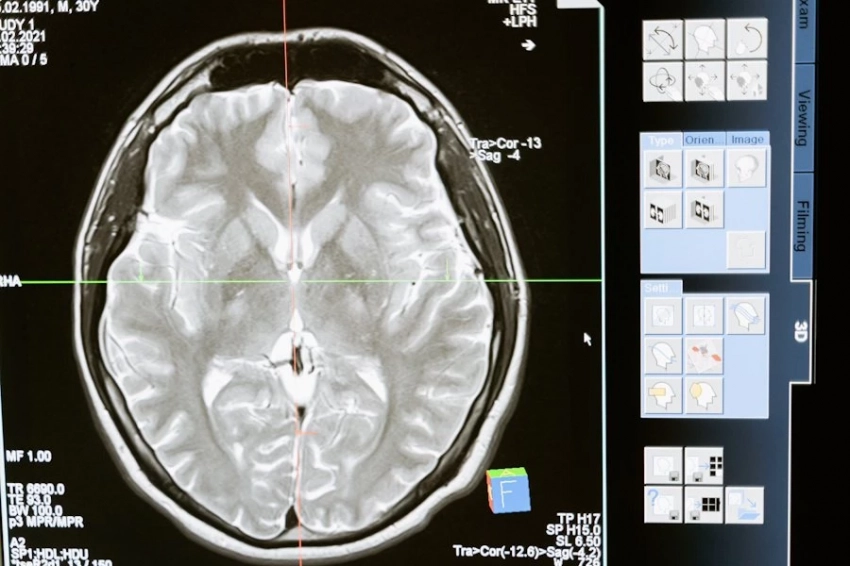

Результаты показали, что у людей, которые смотрели телевизор по пять и более часов в день, вероятность развития деменции увеличивалась в 1,44 раза, болезни Паркинсона — в 1,28 раза, а инсульта — в 1,12 раза. Также было обнаружено уменьшение объема серого вещества мозга и гиппокампа, что связано с ухудшением когнитивных функций.